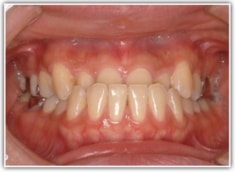

治療後(1年6ヶ月後)